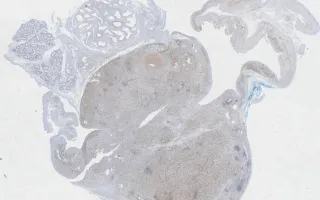

An 18 year-old male presents with an irregular paratesticular mass.

Rhabdomyosarcoma is a malignant tumour of skeletal muscle differentiation of which embryonal is the most common type, comprising 60% of cases. The tumor is most common in children under the age of 10 and is most frequently seen in the head and neck region or genitourinary tract. A wide range of differentiation may be seen. Many tumors have a primitive ‘small round blue cell’ appearance, with alternating areas of myxoid hypocellularity, while others have a predominant spindle cell morphology (seen here) with more easily identifiable rhabdomyoblasts.

Sections demonstrate a malignant, large spindle cell neoplasm centred on the spermatic cord with fascicular

architecture and moderate-to-marked pleomorphism (anaplasia) and occasionally multiple nucleoli. These features signify the anaplastic variant in this case, which is associated with a worse prognosis. Scattered elongated rhabdomyoblasts with cytoplasmic cross-striations and globoid rhabdomyoblasts are identified. In many cells the cytoplasm appears vacuolated. Mitotic figures are easily identified (13/10 HPF), including atypical figures. Necrosis is focally present.

By immunohistochemistry the tumor cells are positive for SMA, desmin, and myogenin (MYF4), confirming skeletal muscle differentiation. Molecular testing failed to detect the two most common translocations associated with alveolar rhabdomyosarcoma (PAX3-FOXO1; PAX7-FOXO1), essentially excluding this subtype from the differential diagnosis.

This slide shows myogenin stain. See Related Content for H&E, SMA and desmin stains.